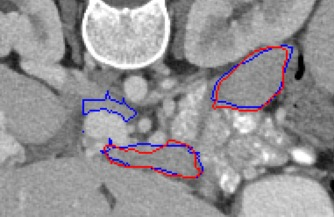

Automated segmentation in medical image analysis is a challenging task that requires a large amount of manually labeled data. However, most existing learning-based approaches usually suffer from limited manually annotated medical data, which poses a major practical problem for accurate and robust medical image segmentation. In addition, most existing semi-supervised approaches are usually not robust compared with the supervised counterparts, and also lack explicit modeling of geometric structure and semantic information, both of which limit the segmentation accuracy. In this work, we present SimCVD, a simple contrastive distillation framework that significantly advances state-of-the-art voxel-wise representation learning. We first describe an unsupervised training strategy, which takes two views of an input volume and predicts their signed distance maps of object boundaries in a contrastive objective, with only two independent dropout as mask. This simple approach works surprisingly well, performing on the same level as previous fully supervised methods with much less labeled data. We hypothesize that dropout can be viewed as a minimal form of data augmentation and makes the network robust to representation collapse. Then, we propose to perform structural distillation by distilling pair-wise similarities. We evaluate SimCVD on two popular datasets: the Left Atrial Segmentation Challenge (LA) and the NIH pancreas CT dataset. The results on the LA dataset demonstrate that, in two types of labeled ratios (i.e., 20% and 10%), SimCVD achieves an average Dice score of 90.85% and 89.03% respectively, a 0.91% and 2.22% improvement compared to previous best results. Our method can be trained in an end-to-end fashion, showing the promise of utilizing SimCVD as a general framework for downstream tasks, such as medical image synthesis and registration.